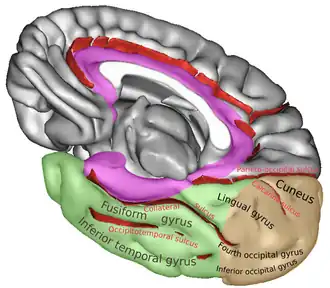

Medial surface of right cerebral hemisphere. Collateral sulcus divides limbic (purple) and temporal lobe (green). | |

The collateral fissure is a large sulcus on the tentorial surface of the cerebral hemisphere and extends from near the occipital pole to within a short distance of the temporal pole. It is also known as the medial occipitotemporal sulcus.[1]

Behind, it lies below and lateral to the calcarine fissure, from which it is separated by the lingual gyrus; in front, it is situated between the parahippocampal gyrus and the anterior part of the fusiform gyrus.